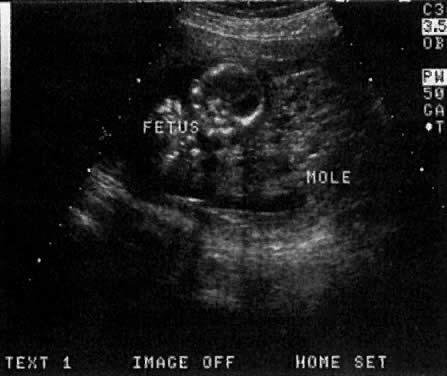

MOLAR PREGNANCY

The characteristic “grapelike clusters” or vesicular pattern seen in molar pregnancy is easily identified on TVS (Fig. 15). In rare cases, a molar pregnancy will be noted concomitant with a normal twin pregnancy. For a discussion of the management of these cases, the reader is referred to the article by Fishman and associates30 (Fig. 16).

Fig. 16. A normal twin (placenta not in view) shown adjacent to a molar pregnancy.